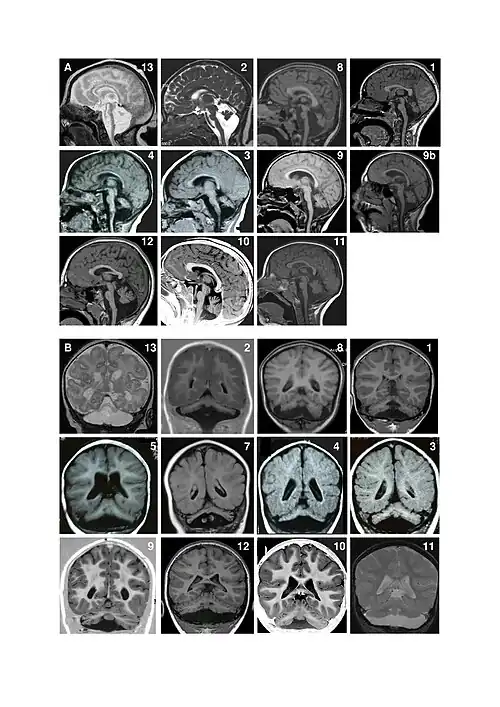

Pontocerebellar hypoplasia (PCH) is a heterogeneous group of rare neurodegenerative disorders caused by genetic mutations and characterised by progressive atrophy of various parts of the brain such as the cerebellum or brainstem (particularly the pons).[1] Where known, these disorders are inherited in an autosomal recessive fashion. There is no known cure for PCH.[2]

There are different signs and symptoms for different forms of pontocerebellar hypoplasia, at least six of which have been described by researchers. All forms involve abnormal development of the brain, leading to slow development, movement problems, and intellectual impairment.[2]